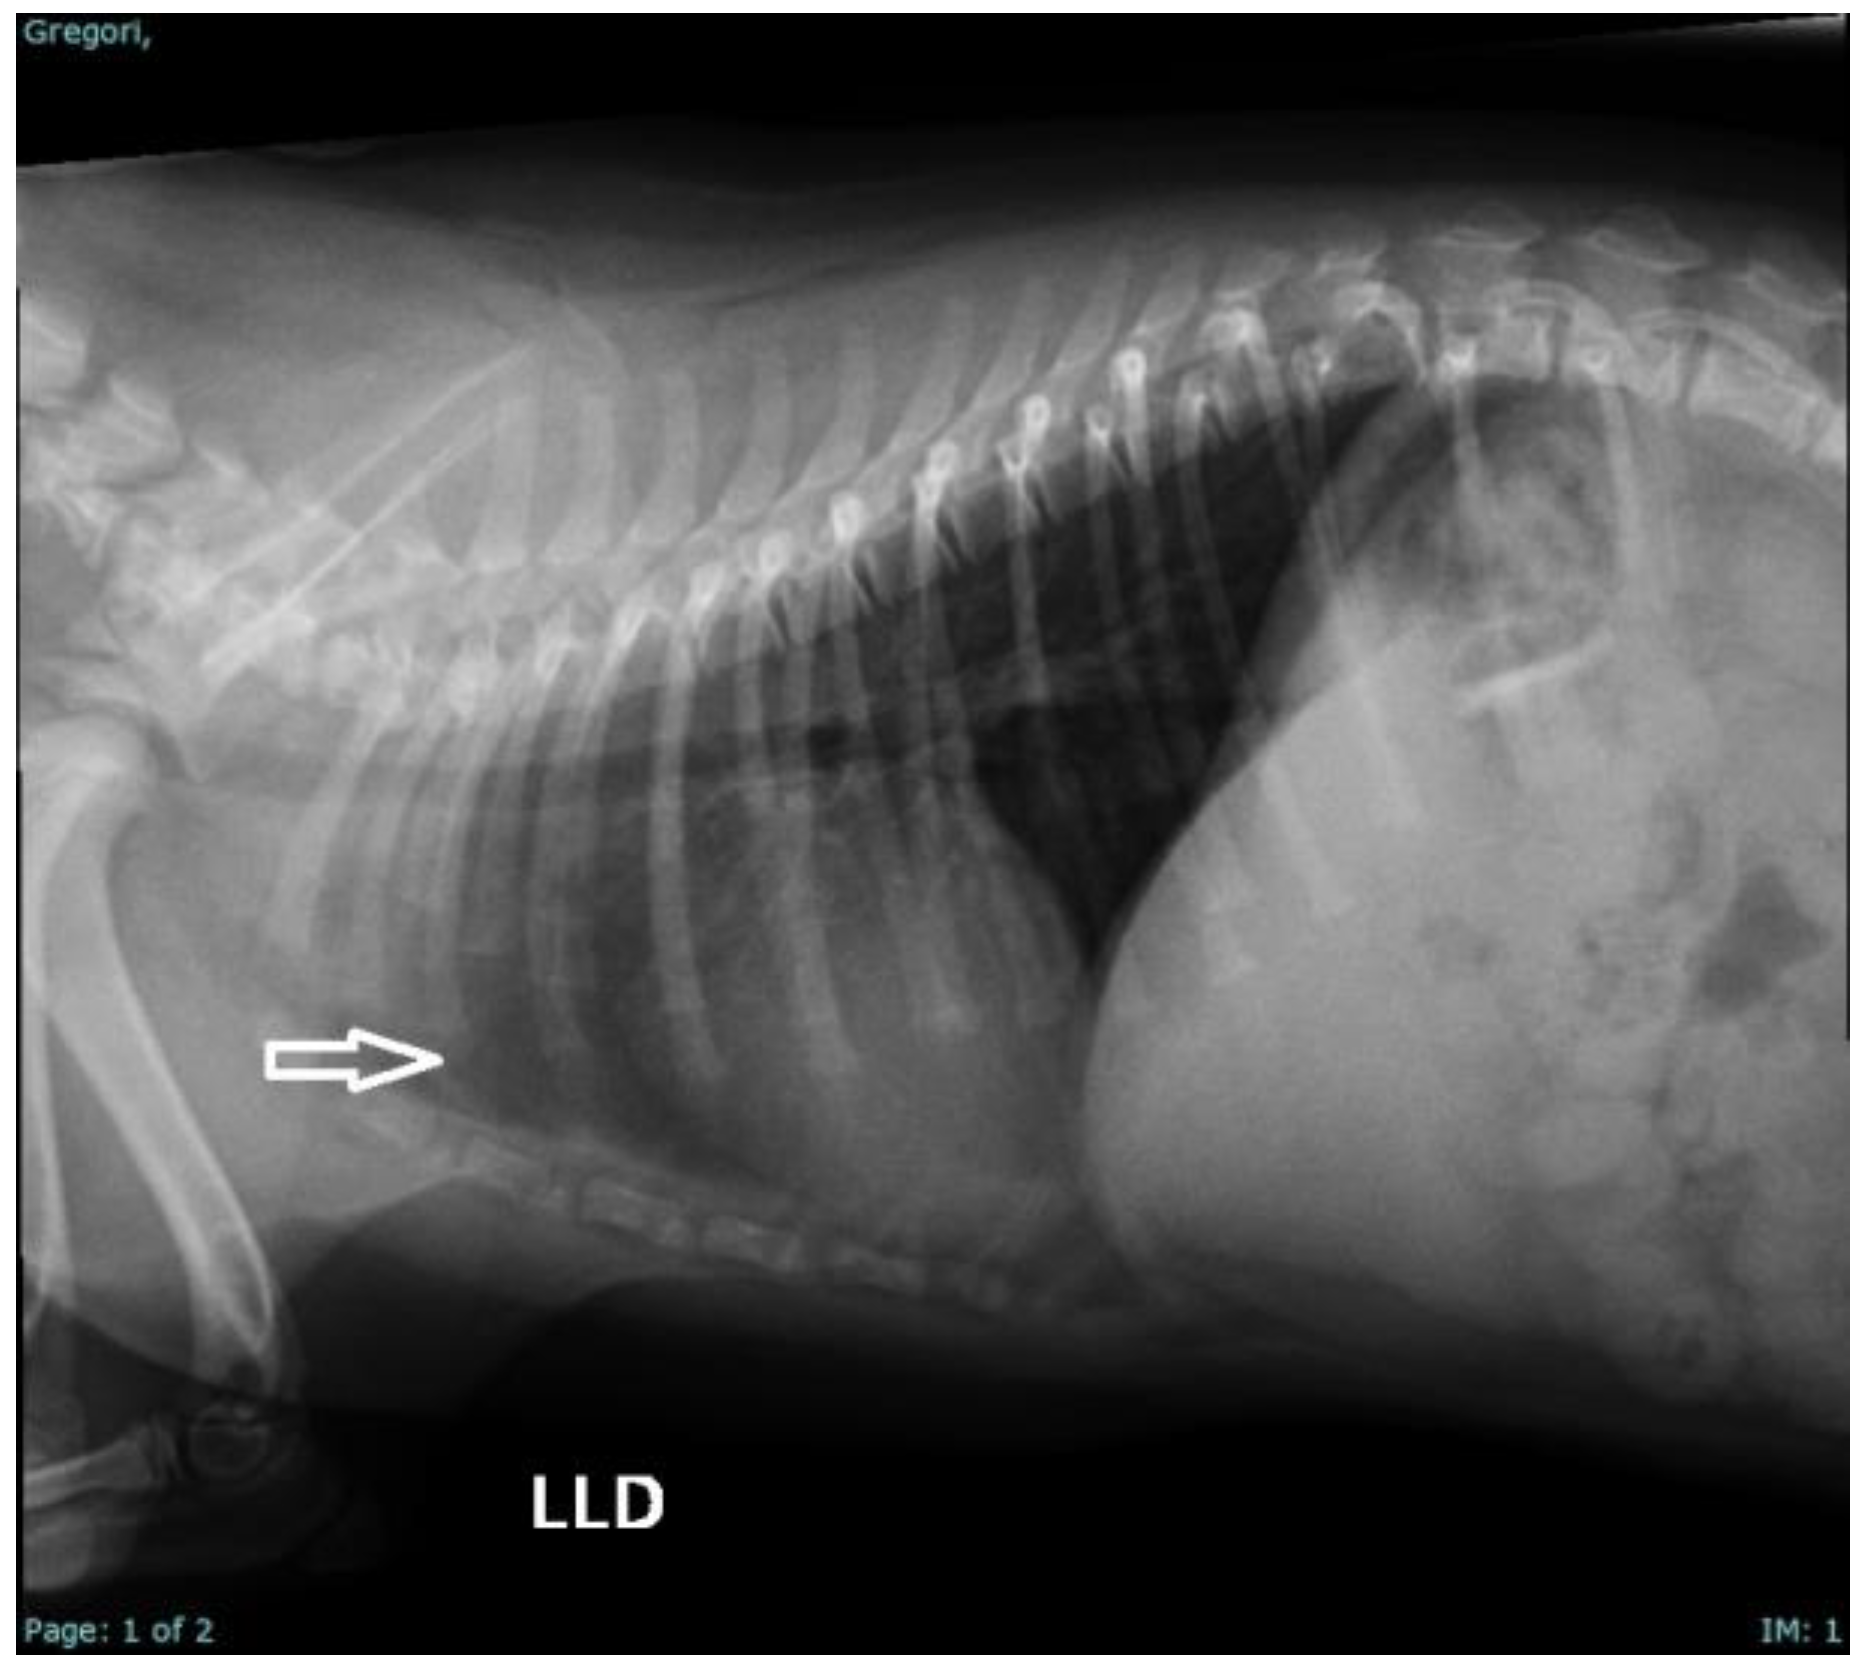

| 9 | Pug | Male | At 2 days of life | Sepsis, dyspnea, pulmonary crackles, neonatal triad, and weak sucking | Clinical management + Amoxicillin + clavulanate (20 mg/kg/BID/7 days); N-acetylcysteine (3 mg/kg/PO/TID, for 5 days) and Nebulization (TID) [44] |

| 10 | Pug | Male | At 14 days | Sepsis, dyspnea, pulmonary crackles, neonatal triad, weak sucking, and hydrocephalus | Clinical management; Amoxicillin + clavulanate (20 mg/kg/BID/7 days); N-acetylcysteine (3 mg/kg/PO/TID, for 5 days); Nebulization (TID); Prednisolone (0.5 mg/kg/PO/BID/7 days); Omeprazole (1 mg/kg/PO/SID); Furosemide (2 mg/kg/BID/2 days) [44] |